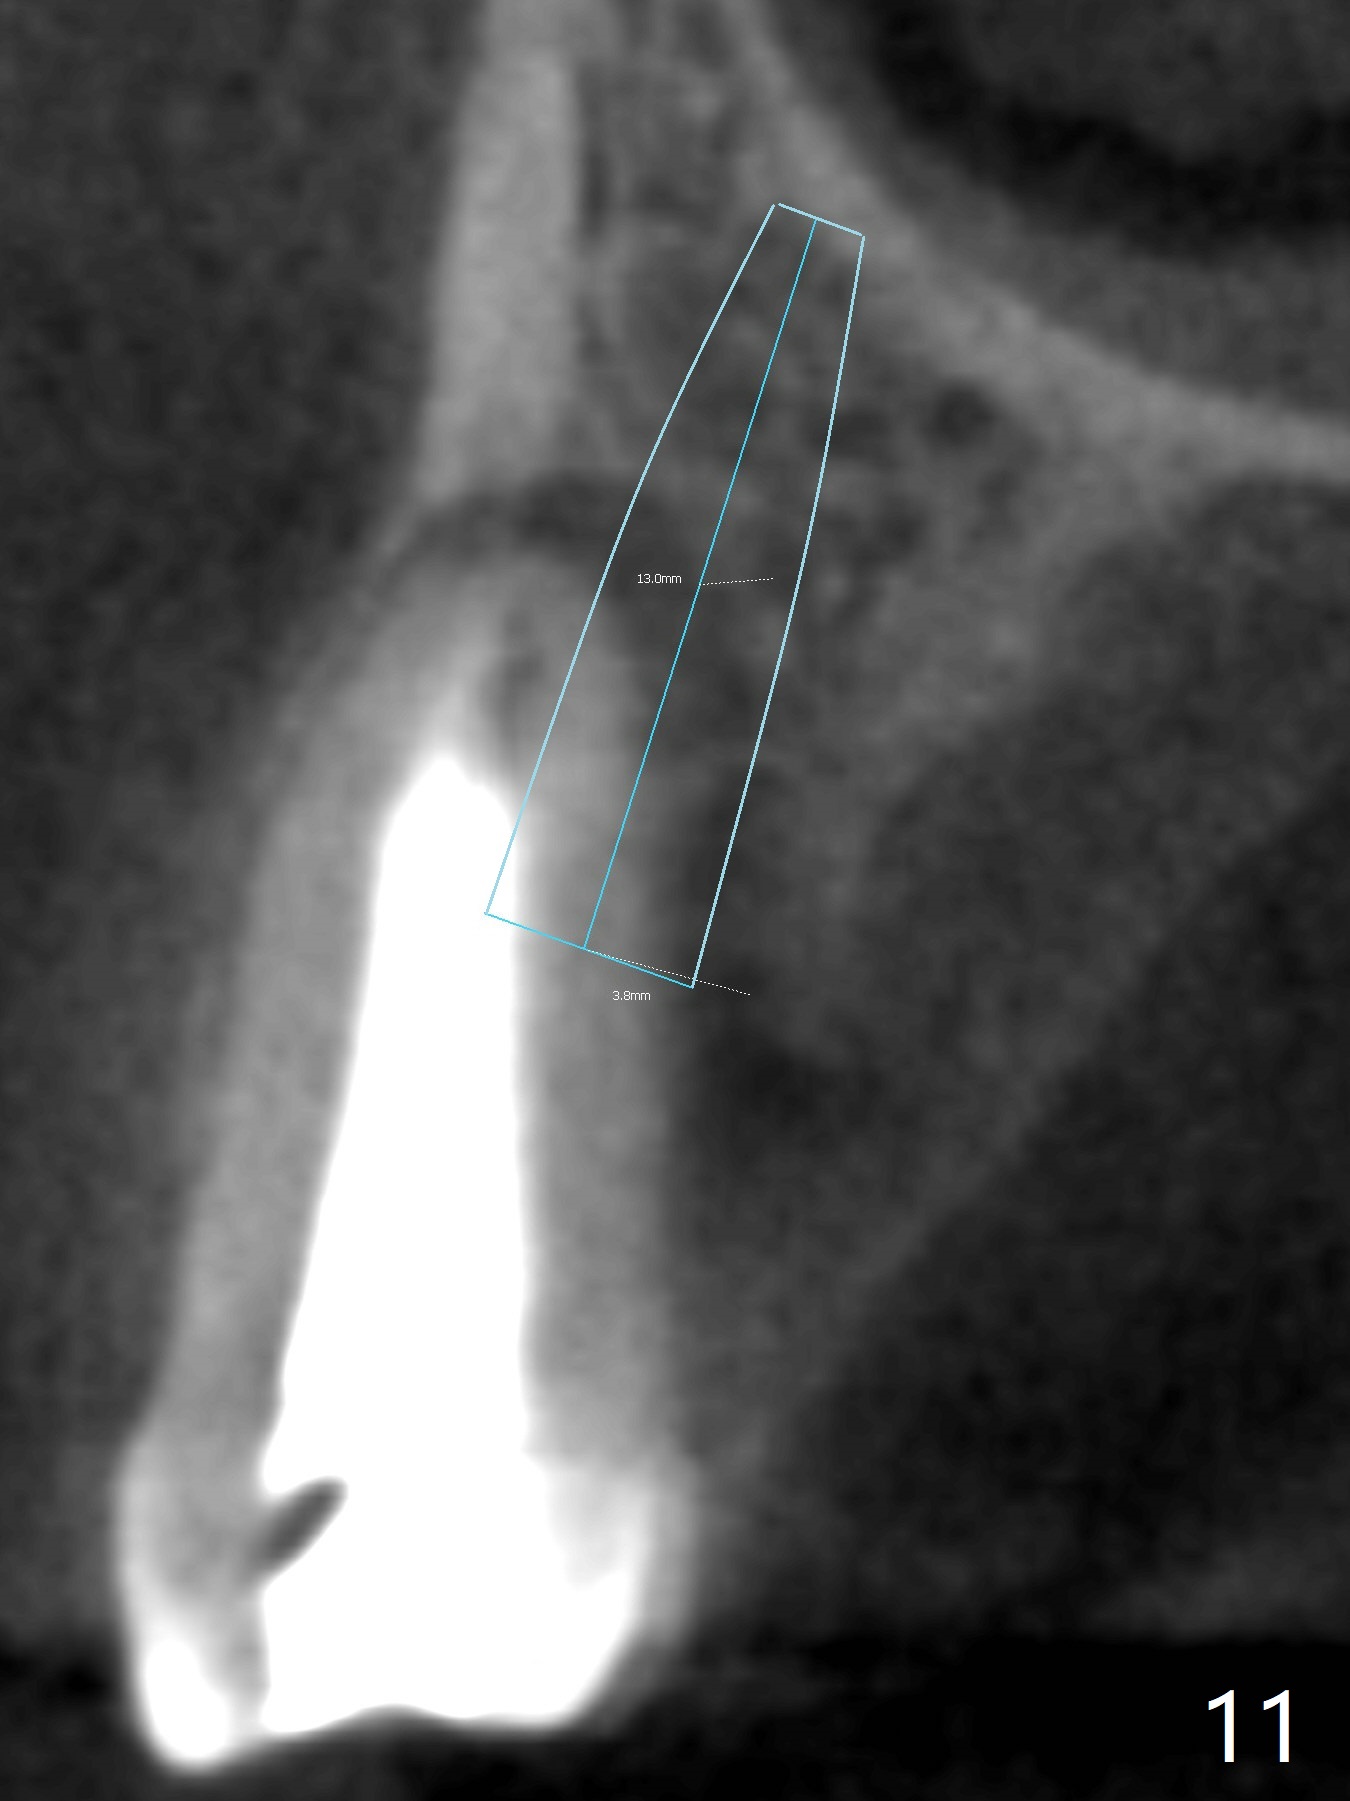

In fact there is a small buccal fistula, which is communicated with the underlying implant threads. Although preop CT shows that the buccal crest is lower than the palatal (3.8x13 mm, Fig.10 P) one, intraop finding of missing buccal plate should dictate a shorter implant (Fig.11) or onlay graft to avoid periimplantitis. Regeneration of the bone plate is limited. Later the fistula disappears with formation of a concavity (Fig.13). There is no symptom. Is bone graft necessary with a remote incision? 3-D images of CT taken 1 year 5 months post cementation show possible mesiobuccal and distopalatal bony defects (Fig.13-16). It is possible that bone graft was placed enough palatal (Fig.16). DO composite at #3 is redo satisfactorily (Fig.17 *).